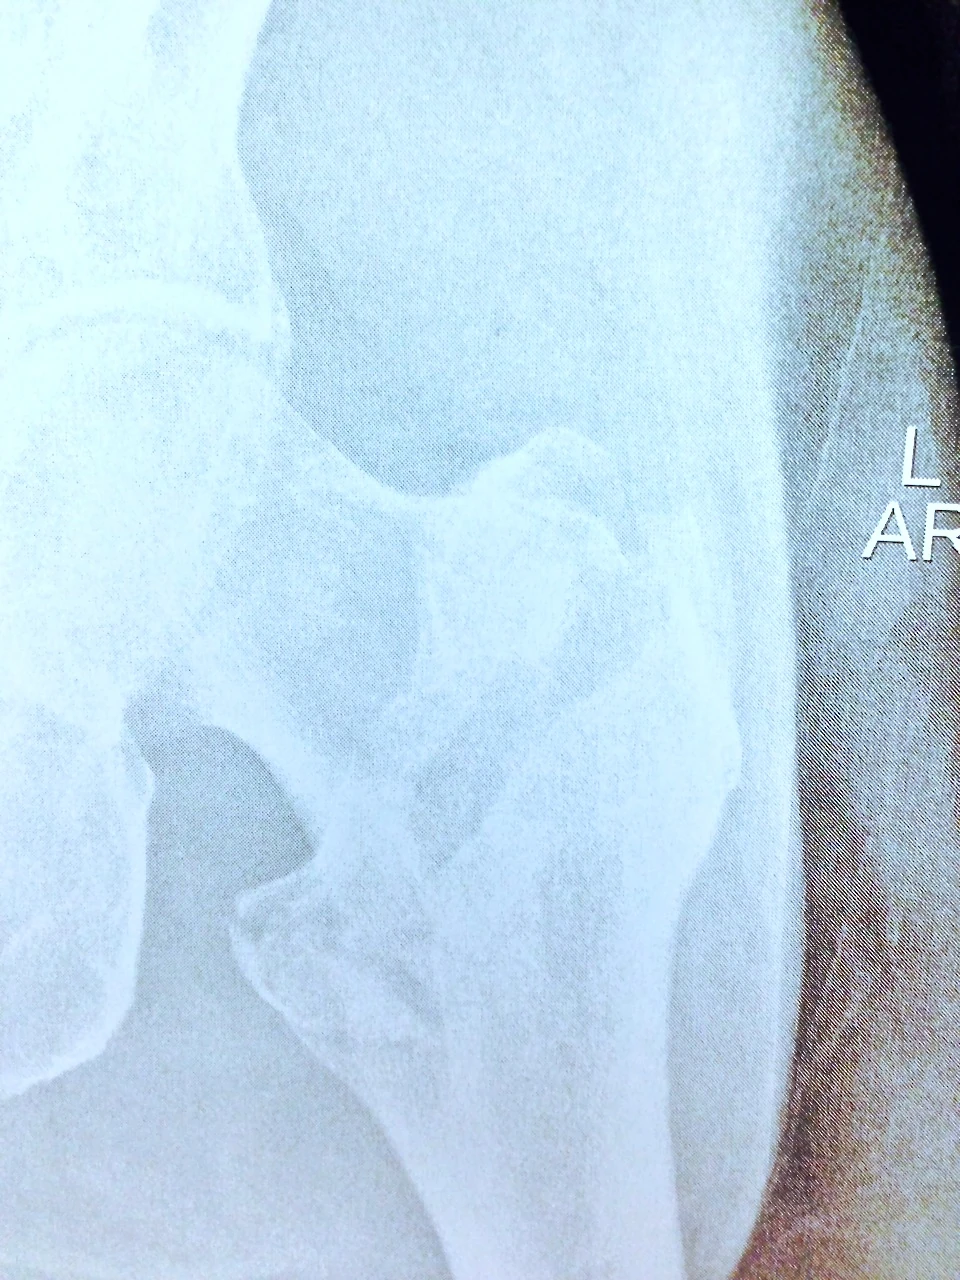

I don’t have a photo of the post operation hip, just the broken one. In the photo below, the break is the dark area at the top of my leg bone, where it angles to the left. They put in two long screws through the femur, into the head of the hip, to pull the whole thing back together, then a plate and three more screws below it to strengthen the whole area, I guess. I wonder what would happen if/or more accurately, will happen, when I fall on that stainless steel plate. Maybe there will be enough soft tissue around the area, the plate is deep enough, so it just doesn’t come poking through the skin? I wonder if I’m going to set off metal detectors at the airports now? That would be weird.

Steve sustained a 2 part intertrochanteric fracture of the hip. The fracture was fairly stable secondary to the fact the fracture line was somewhat horizontal than vertical. the more vertical the fracture line the less stable the fracture. There are 2 major types of hip fractures and the classification is based on anatomic location. There are fractures that involve the femoral neck and fractures that involve the intertrochanteric region of the hip. Femoral neck fractures are problematic secondary to the fact the major blood supply of the femoral head, the ball of the hip, runs through that region: the medial femoral circumflex artery. When a femoral neck facture occurs it can and usually does disrupt the blood supply to the femoral head cause avascular necrosis or death of the bone. If a young patient has a femoral neck fracture we like to try to surgically fix the fracture but tell the patients it may fail and ultimately they would need a conversion surgery to a hemiarthrplasy or a total hip replacement. In the older patient population we typically default to a hemiarthrplasty. Fortunately in Steve’s case his fracture location was in the intertrochanteric region therefore the blood supply to the femoral head is not disrupted and an ORIF could be performed. Potential issues with the surgery is if the hip is not reduced back to its normal anatomical position and heals rotated it will affect knee alignment. So every time Steve has a pedal stroke it would irritate his knee, that is why he needed an expert like Dr. Matt Karam to perform his surgery. Fortunately he fractured his hip in an area of the country where it is a powerhouse of orthopaedics. Special thanks to Dr. Karam for agreeing to accept Steve as a patient in transfer and Dr. Ned Amendola , who is head of Sports Medicine at Iowa for hooking me up with Dr, Karam to arrange the transfer. I have no doubt that Steve will be jamming on his bike before we know it!